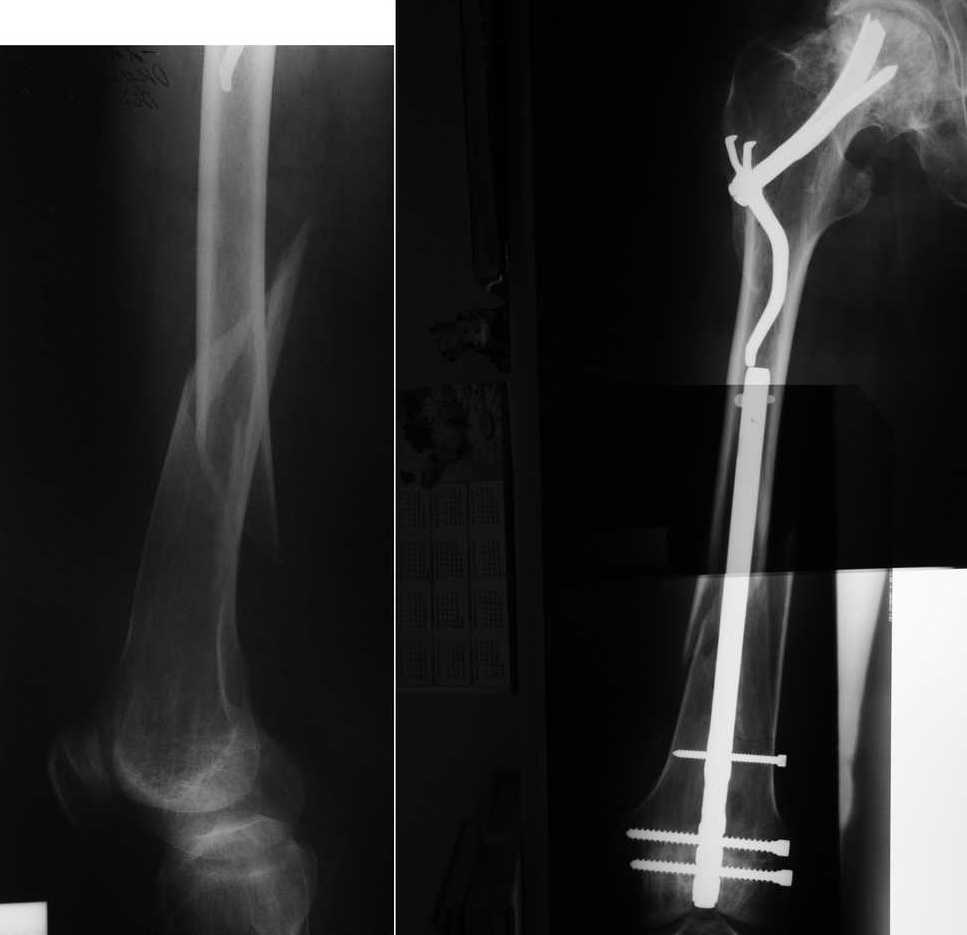

Отдалённый результат забытого метода

Хотим напомнить о забытом, эффективном методе остеосинтеза медиальных переломов шейки бедренной кости. Пациенту 55 лет был выполнен остеосинтез медиального перелома шейки бедренной кости фиксатором Сеппо 15 лет назад. В течение этих лет пациент жил не тужил, пока в марте сего года не получил перелом диафиза этого же бедра. Мы сочли единственно возможным применение в данной ситуации метода остеосинтеза штифтом с ретроградным введением. С удовольствием выслушаем ваши мнения. Возможно у кого-то ещё есть опыт применения фиксаторов Сеппо. Доктор Головач О. Н., доктор Савочкина М. А., г. Дзержинский, Подмосковье.

А с какой целью дистальное блокирование произведено в медиально-латеральном направлении, а не наоборот, как рекомендуется любым производителем? Хочется надеяться, что проксимальный винт проведен спереди назад, а не наоборот...

Уважаемый Алексей Юрьевич. Приносим свои извинения за неверное сопоставление двух рентгеновских пленок. Конечно же дистальное блокирование произведено с латеральной стороны.

Проксимальный винт введен спереди назад. Спасибо за внимательность!